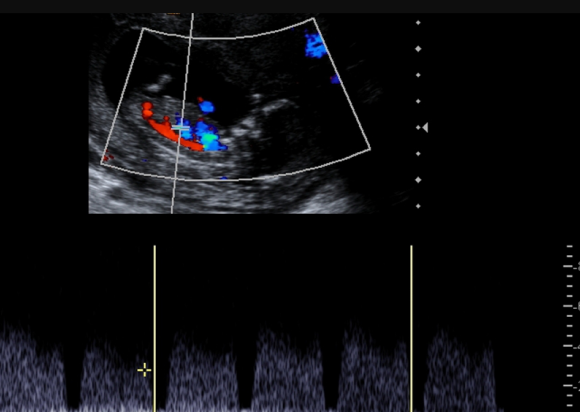

Fetal Growth and Dopplers

It’s a detailed scan of baby’s heart. This scan ensures baby’s heart is developing and functioning in normal manner.

This is usually done at 22 weeks, but can be offered earlier or later as needed.